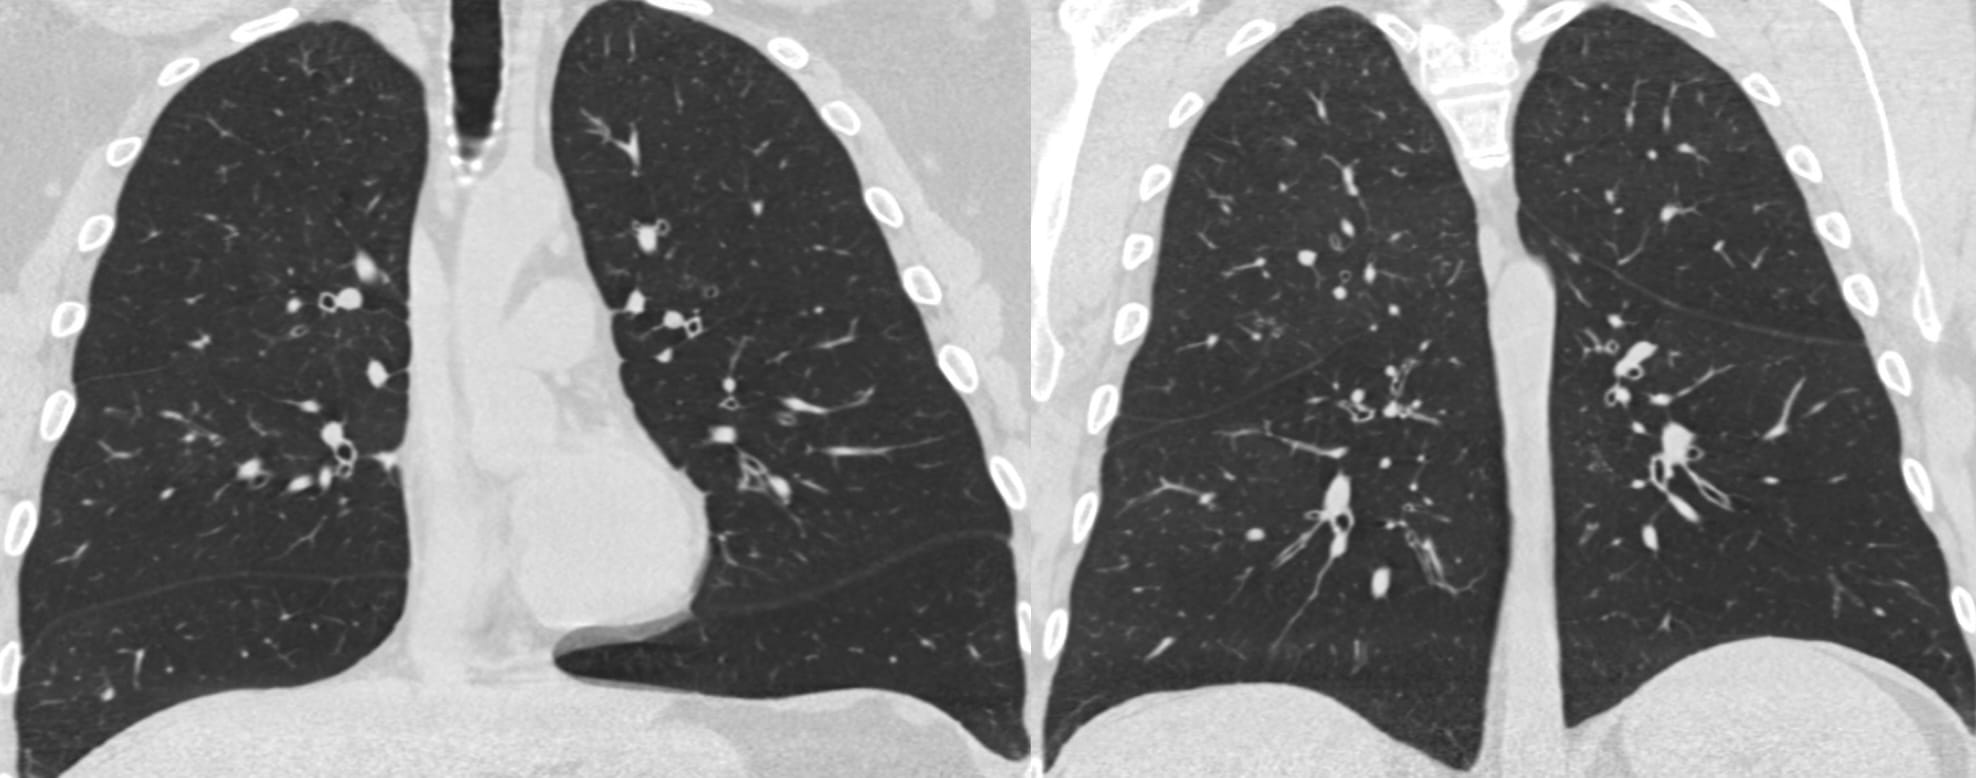

Note the predominant involvement of the upper lungs.

The very definition of an Aunt Minnie

Another Aunt Minnie

It’s a matter of how many I put there with my macrophage spray can…